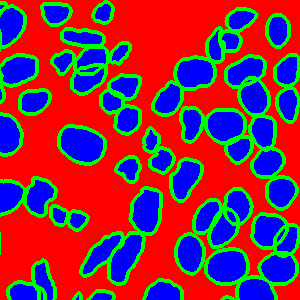

The task of nuclei segmentation can be roughly divided into two stages: the first stage is extracting the foreground(nuclei), the second stage is segmenting the connected foreground area into separated nuclei and finding out the boundary of each nucleus. Our method intends to merge these two steps by extracting the nuclei and their edges at the same time. That is the reason why it is named ”nuclei-boundary(NB) model”. As shown in Fig.3, the output of the NB model has three channels, each has the same height and width with the input image. Its values represent the probabilities of each pixel being , or class, respectively. The manual annotation for our segmentation problem is the boundary of each nucleus. A pixel belonging to the class means that it is on or inside an annotated boundary and within 2 pixel from the boundary. Pixels of the class are those that are inside annotated boundary but are not pixels. Correspondingly, the output can be regarded as an RGB image and the estimated maps of the , and are represented by red, green and blue, respectively, as shown in Fig.3. To generate the ternary mask for training, we apply a morphology operator to each nucleus to obtain the pixels, and then subtract pixels from the nucleus to get pixels.

Figure 6 shows how our method segments the nuclei step by step. The color variety is well controlled by the color normalization procedure. The prediction result shows clear nuclear areas and nucleus boundaries. In the final segmentation result and ground truth image, each nucleus is represented by a different color.